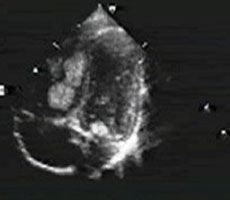

8、日齢5の新生児、チアノーゼを主訴に入院。心エコー図を示す。この疾患で認められる可能性のある所見のなかで誤っているのはどれか。2つ選べ。

- 類洞交通

- 心房間での右左短絡

- 動脈管での左右短絡

- 心房中隔と心室中隔の非整列

- 心室中隔流入路の短縮(スクーピング)

正解:d, e